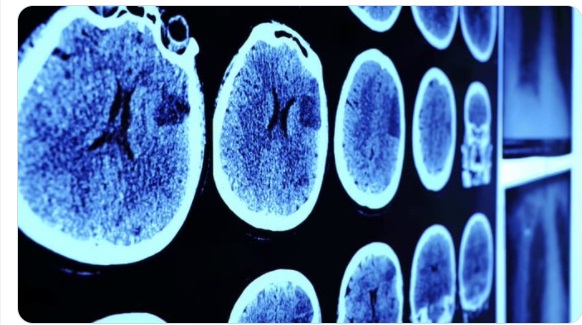

تهران- الکوثر:  شرکت داروسازی «مدرنا» از آغاز آزمایش‌های بالینی واکسن ویروس اپشتاین-بار (Epstein-Barr) عامل احتمالی ابتلا به اسکلروز چندگانه (ام. اس) بر روی انسان خبر داد.

اسکلروز چندگانه نوعی بیماری خود ایمنی در سیستم عصبی مرکزی (مغز و نخاع) است که باعث اختلال در سیستم ایمنی بدن می‌شود و به میلین، غلاف محافظ تار‌های عصبی آسیب می‌رساند.

شرکت داروسازی «مدرنا» هفته گذشته از آغاز آزمایش‌های بالینی واکسن ویروس اپشتاین-بار (Epstein-Barr) روی انسان خبر داد.